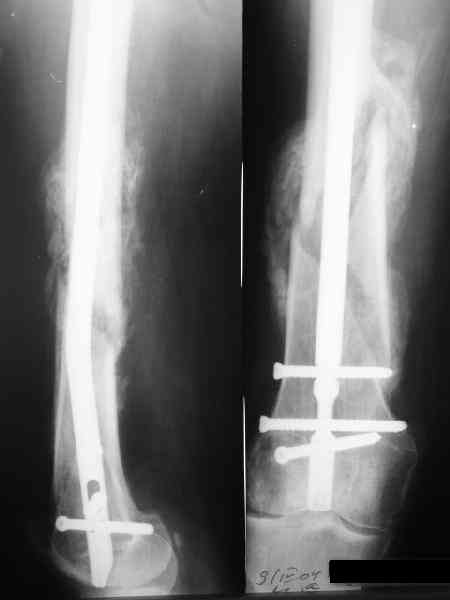

Да, действительно красивый клинический пример: виден вальгус до операции и последующая коррекция углового смещения на "полярах". Я так понимаю, что в вашей клинике есть возможность использовать различные фиксаторы. Почему не использовали DFN? Спицы какие используете? Киршнера или Илизаровские? С виду очень тонкие...

> фиксаторы. Почему не использовали DFN?

В смысле, почему не ретроградно? При дистальных переломах или их последствиях и так с коленом может быть не все в порядке, и чрессуставное введение гвоздя состояние колена как имнимум не улучшает. Поэтому наиболее дистальные как раз штифтуем обычно антеградно. Хотя 20-25% бедер штифтуем ретроградно, но более проксимальных.

А на DFN свет клином не сошелся, мы используем отечественные штифты (MetaDiaFix, "ЦИТО"), которые можно вводить и ретроградно (4 винта), кроме того, в качестве ретроградного бедренного замечательно подходит большеберцовый гвоздь диаметром 12 мм.

В приложении как раз видна эволюция использововшихся у нас большеберцовых гвоздей. Первый - дизайн как у UTN, второй - разнесены 45 градусные отверстия (зачем их вообще изначально так нелепо на одном уровне сделалм???), третий - убрано сиавшее лишним статическое отверстие, Herzog's bend перемещен более проксимально.

Насколько я помню, мы использовали этот вариант после знакомства с гвоздями SIGN, которые вообще одинаковые для бедра и голени, и дизайн у них большеберцовый.